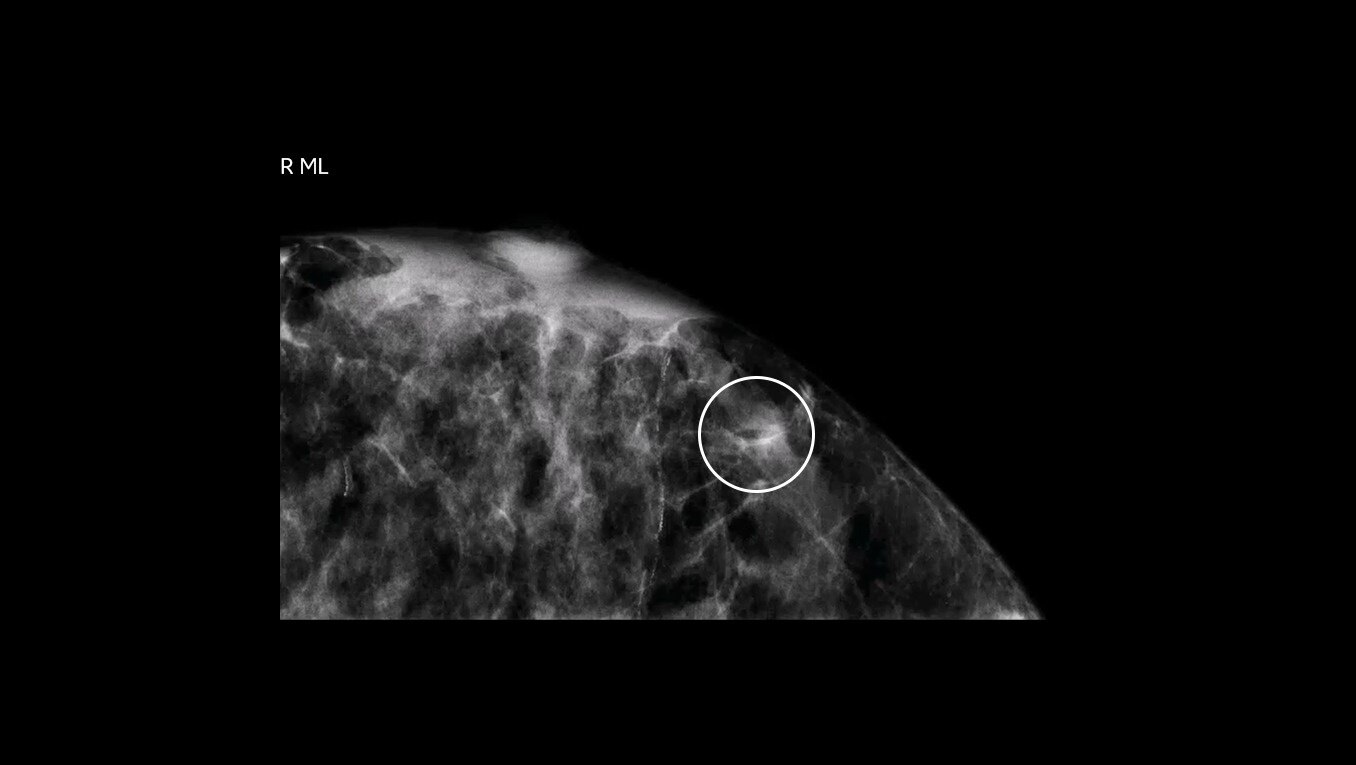

Find answers sooner

Shorten the time to biopsy and diagnosis

No more delays waiting for MRI availability or enduring lengthy 60-90 minute5 MRI-guided breast biopsy procedures. CEM guided biopsy can be performed within 15 minutes from first image to clip placement image6. A shorter biopsy lead time and quicker biopsy procedure may speed up a definitive diagnosis and faster path to treatment.